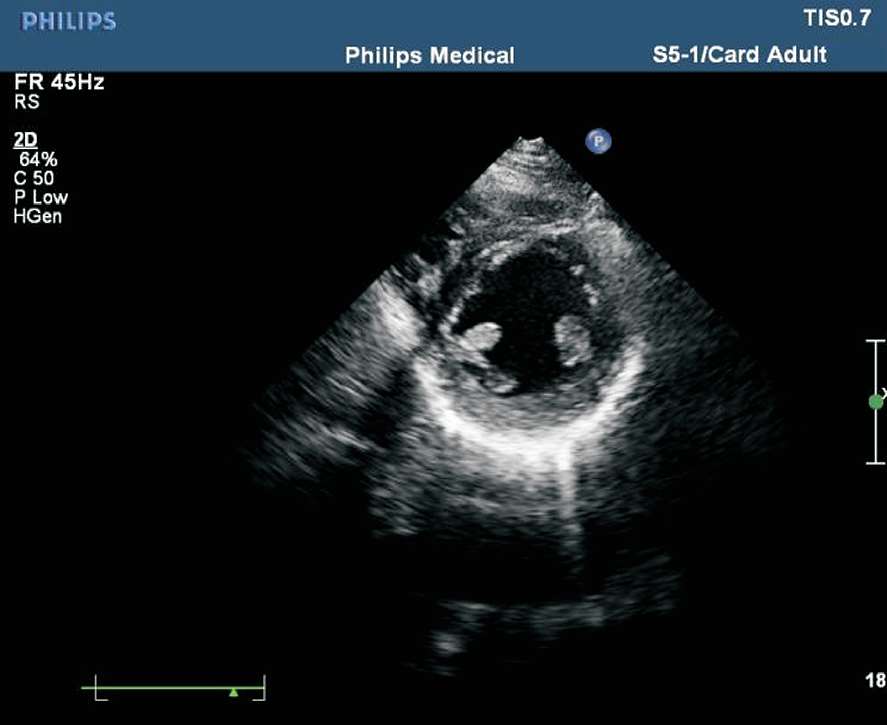

患者取左侧卧位或平卧位,探头置于胸骨左缘第2~3 肋间,声束垂直于胸骨旁左心室长轴切面。在此切面可观察主动脉瓣的形态、厚度、回声强度及开闭状态,右心室流出道与肺动脉干有无增宽、狭窄,降主动脉与肺动脉之间有无异常通道,肺动脉瓣的形态及活动(见图1-27)。正常主动脉瓣呈三瓣叶,收缩期开放为“▽”形,舒张期关闭为“Y”形(见图1-28)。

图1-27 心底大动脉短轴切面(RA:右心房;RV:右心室;PA:肺动脉;AO:主动脉;LA:左心房)

图1-28 心底大动脉短轴切面主动脉瓣呈三瓣叶,舒张期关闭为“Y”形